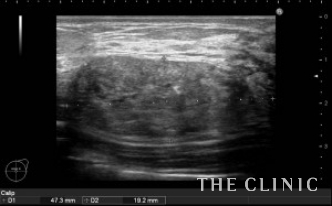

2年前に他院にて片側300㏄ずつの脂肪注入を受けられています。注入後、間もなくしこりを感じるようになり、今回はしこり除去の目的で当院を受診されました。右胸にはオイルシストと充実性のしこり、左胸には47.3㎜の充実性のしこりを認めました。(オイルシストの症例はNo.24でご紹介します)